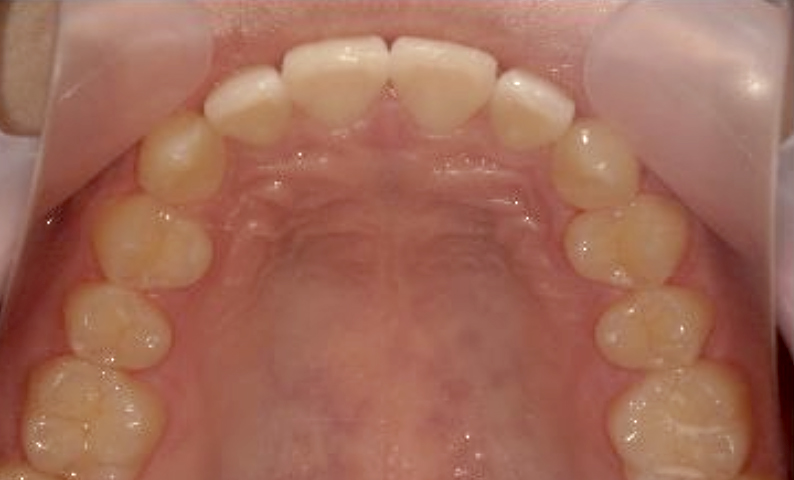

症例_010 上顎だけの部分矯正

治療期間:9ヶ月金額:30万円+税女性前歯のガタガタ捻転歯上の前歯だけ